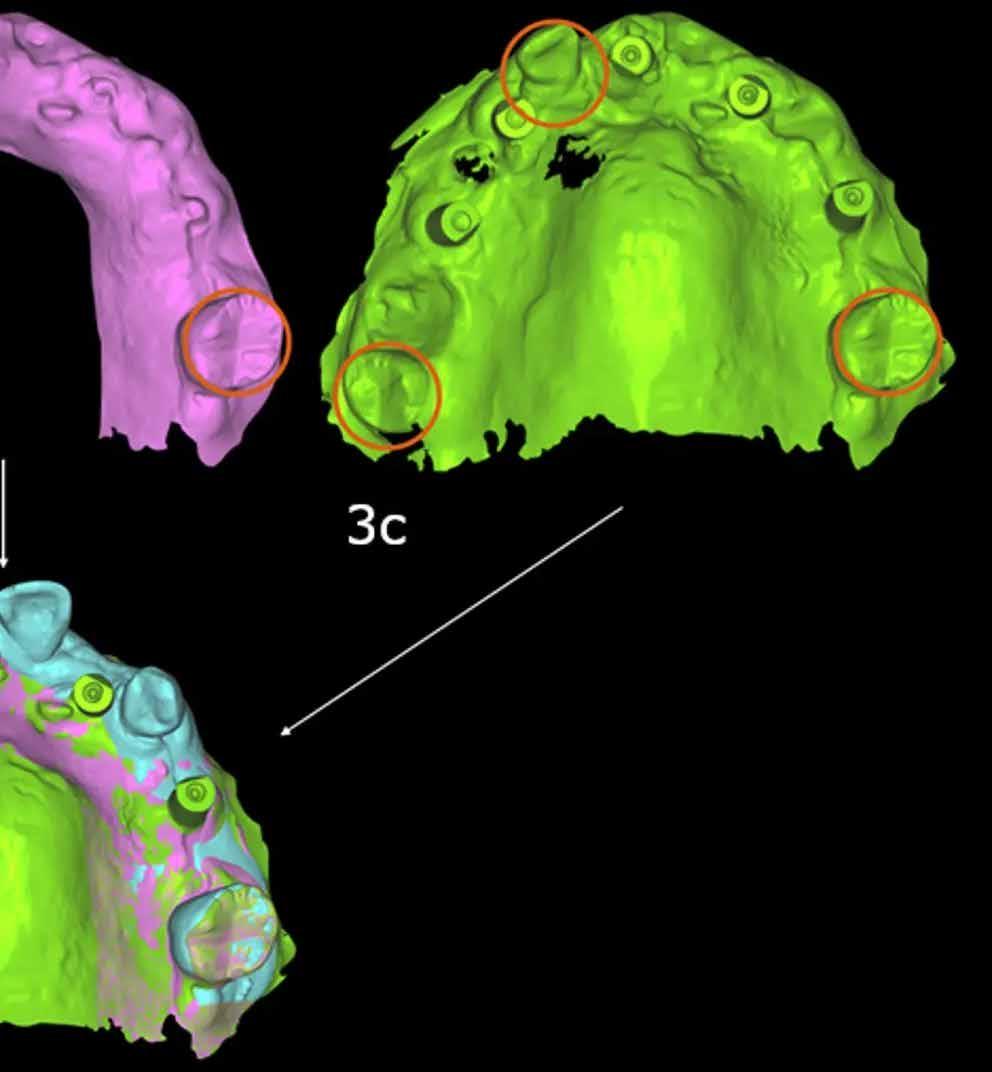

2. a és b ábra: A műtét előtti maxilláris intraorális felvétel (a). Műtét előtti felvétel a digitális wax-uppal (b).

1. ábra: Kiindulási helyzet.

3. a–d ábra: A szelektív extrakció három fogat hagyott közös pontként a műtét előtti (a), az ideiglenes (b) és az implantátum intraorális felvételek (c) között, hogy a szoftver egyesíteni tudja a fájlokat, és az implantátum felvételét ugyanabban a 3D térben helyezze el, mint a műtét előtti felvételt, amelyen a wax-up volt.

4. a–d ábra: A műtét előtti maxilláris intraorális felvétel a digitális wax-up (a és b) és az implantátumfelvételen (c és d) a protézisre konvertált digitális wax-up (a és b).